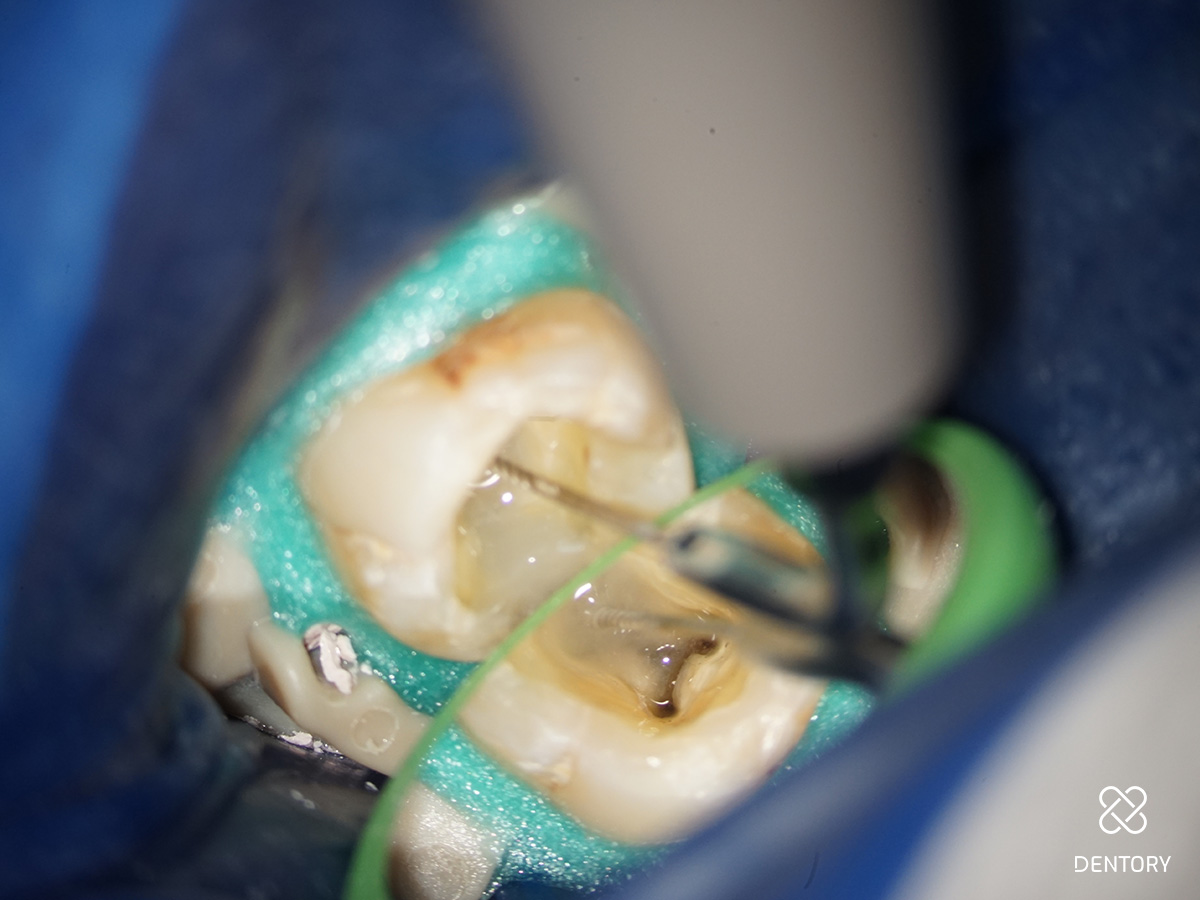

Abbildung 1

Diagnoseaufnahme (alio loco) Regio 37: Symptomatische apikale Parodontitis (PAI 4). Als Besonderheit erkennt man bereits die S-förmige Kanalkrümmung in der mesialen Wurzel und die J-förmige apikale Krümmung im distalen Kanal.